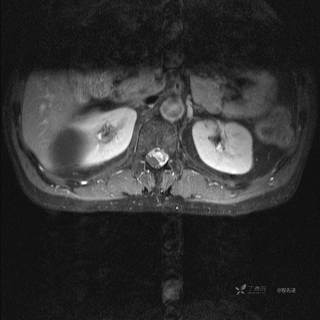

MR

T2

T2压脂

T1

T1增强

T1增强冠状位

T1增强横断位